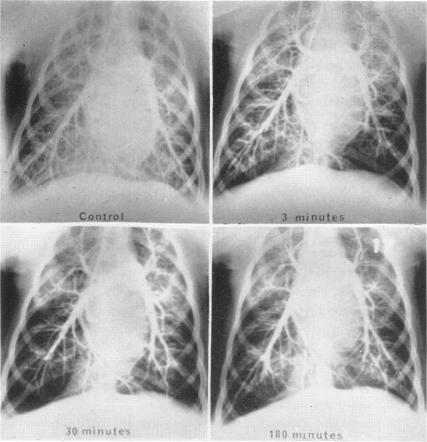

THROMBOEMBOLI AS A CAUSE OF COR PULMONALE.

Bull N Y Acad Med. 1965 Sep;41(9):981-93.